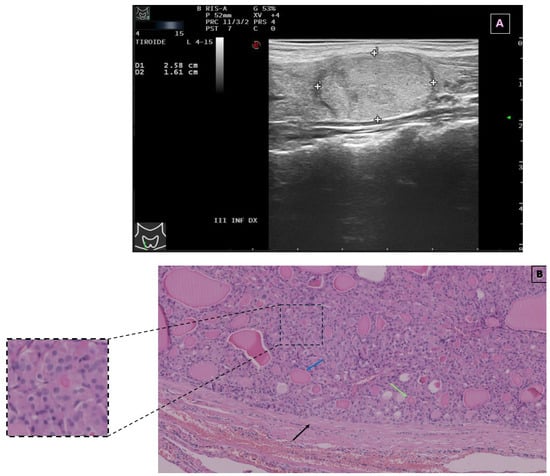

| Current case | 13/Female | 26 × 16 mm | Enlarging neck mass | Bethesda IV (follicular neoplasm with oncocytic features) | Hemithyroidectomy | No recurrence |